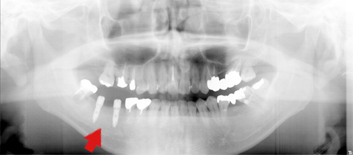

60代男性

左下の奥歯が、C4(歯の根の部分だけ残った状態)で、インプラントを

検討され他の歯科医院からのご紹介で来院されました。

その歯は、歯の根の部分まで割れていて、残すことができない状態でした。

抜歯後、インプラントをしました。

現在では、定期的にメンテナンスに来院され、良好な状態で満足いただいています。